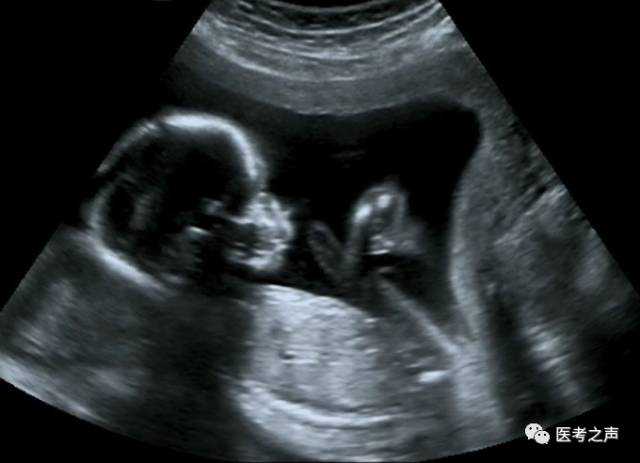

B超

像挑西瓜前敲一敲

B超检查是利用超声波产生回声的原理来检查的。超声能向一定方向上传播,而且可以穿透物体,如果碰到障碍,就会产生回声,人们通过仪器将这种回声收集并显示在屏幕上,可以用来了解物体的内部结构,辅助诊断。就像挑西瓜一样,边敲边看显示病灶情况。B超是两个维度的超声信息,构成平面图形,反映人体结构。

随着彩色-多普勒超声技术的产生,出现了彩超(彩色B超),即在黑白B超的基础上加上彩色多普勒,彩超同时又提供了血流动力学的丰富信息,实际应用受到了广泛的重视和欢迎,彩超在目前临床上经常被使用。

4、腹部盆腔——除肠道外,一般超声都能检查

腹腔器官受呼吸影响较大,进而影响到CT、核磁成像,而超声不会因此受影响。同时,超声对肝脏、脾脏、胰腺、肾脏、盆腔等器官诊断准确率较高。

但是超声受气体干扰很大,对于肠道等含气较多的器官,超声诊断准确率会降低。